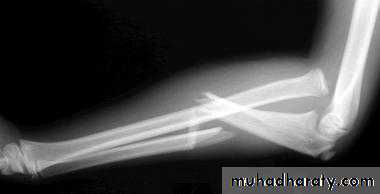

Upper limb

Fall on out stretched hand

Possible complications

Late complication

Rest and physiotherapy